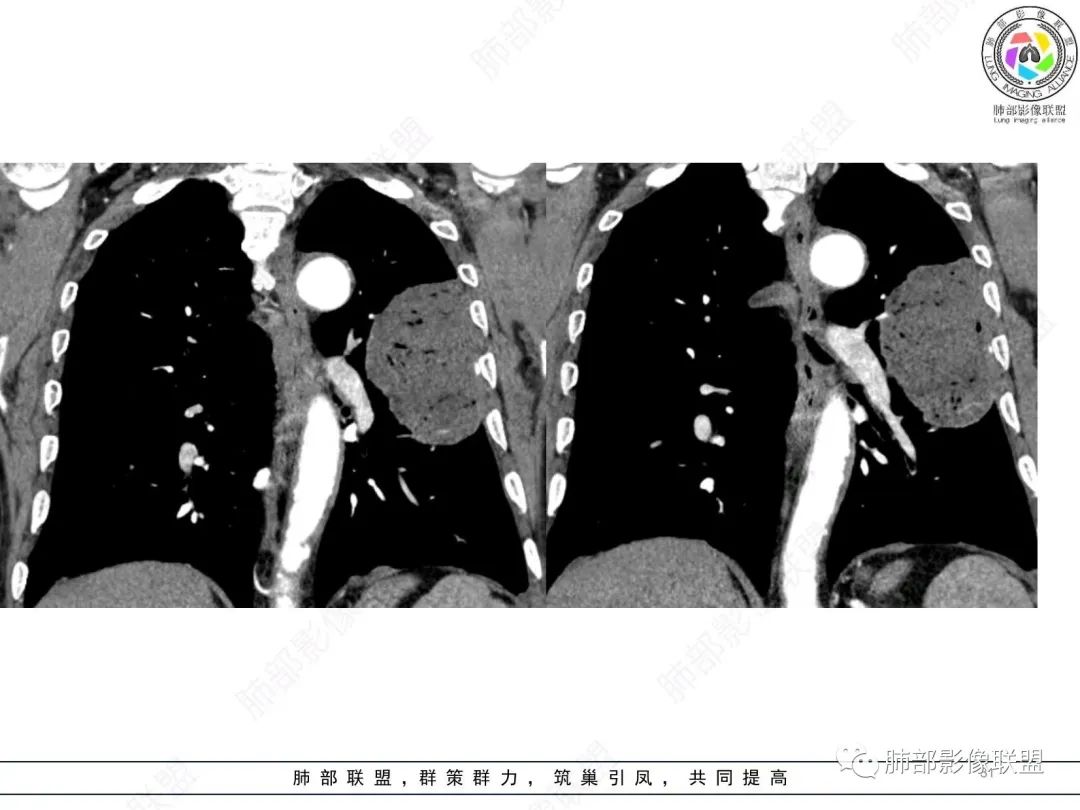

左肺上叶大肿块,膨胀性生长,边界清,密度较低,见部分坏死区,强化弱,肿块见支气管充气V扩张征,分布僵直,枯树枝特点,另一个重要特点血管造影征,淋巴瘤,肿块长轴与胸膜平行,与隐球菌鉴别,隐球荚膜抗原检查,明确诊断经皮肺穿刺。另胸膜钙化(问诊既往有无患胸膜炎病史)。

左肺上叶胸膜下肿块,宽基底与胸膜相连,跨叶裂,边缘清晰膨隆,其内支气管充气,部分扩张、僵直,无明显强化,血管造影征,考虑淋巴瘤,鉴别腺癌

左肺胸膜下巨大占位,跨叶裂,宽基底与胸膜相连,胸膜钙化,平扫密度较低,强化不明显,可见内部血管显影,支气管充气征和扩张,考虑为恶性,倾向于淋巴瘤

左肺上叶胸膜下肿块,膨胀性生长,边界清晰,密度不均部分坏死,未见强化,病灶内支气管迂曲扩张,病灶长轴与胸膜平行,胸膜下脂肪间隙存在,胸膜钙化,考虑放线菌?毛霉?鉴别淋巴瘤

支持淋巴瘤,左上肺大肿块,有分叶,边缘光整,病灶内密度不均,可见支气管扩张征,增强后可见血管影征。周围肺野清晰。

左肺上叶肿块,宽基底与胸膜相连,跨叶裂,边缘清晰膨隆,可见小分叶,其内支气管充气,部分扩张、僵直,呈枯枝征,支气管达边征,增强无明显强化,可见血管造影征,考虑恶性病变,淋巴瘤,鉴别粘液腺癌。